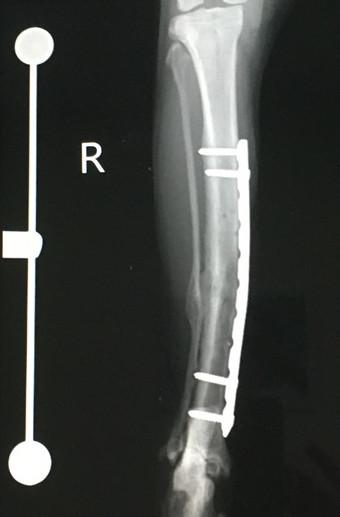

2021年6月、骨折してから約10ヶ月&プレート抜去手術(1回目)から3ヶ月経過しての検診に行ってきました。

レントゲン撮って「順調です」って言われてお会計してくるルーチン。

予定通り次回残りのプレート抜去のスケジュールを決めてきました。

それにしても、プレート抜去予定が7月となると骨折から丸々1年。

ここまでかかるとは予想してなかった(==;。